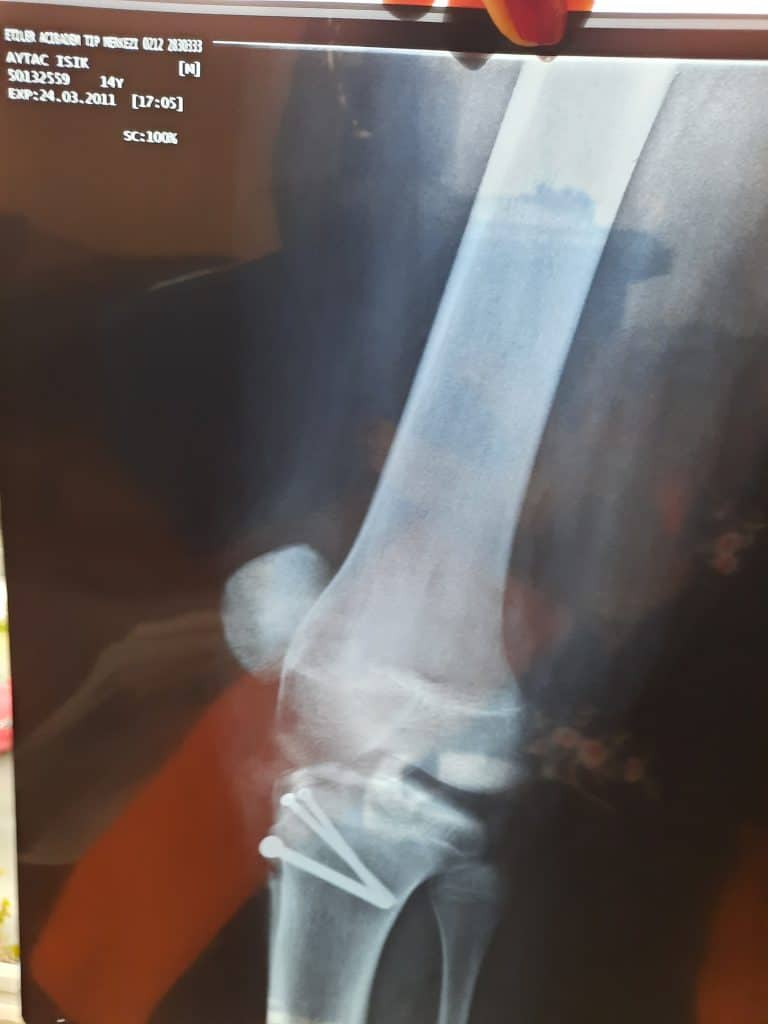

Geçen hafta diz ameliyatımdan bahsetmiştim. Annem okuyunca dizimden çıkan çivileri ve röntgenlerimi çıkarıp bana fotoğraflarını attı.

Çivilerin spiralli olmasına, yani matkapla, dönerek içeri girdiklerine dikkat çekmek isterim.